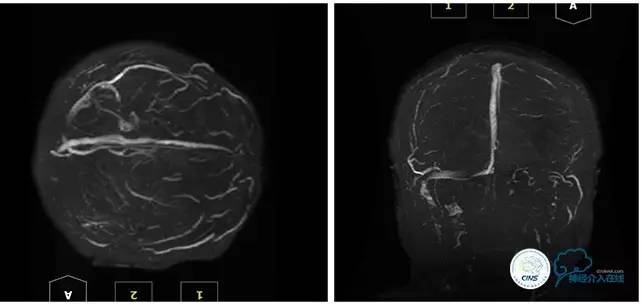

2016-5-19 MRI

2016-05-20 MRV

病史:患者于1年余前,因人流术后出现发作性四肢抽搐伴口吐白沫,头痛及双眼视力降落在外院行颅脑MRI及MRV提示:右侧横窦、乙状窦狭窄,予以低分子肝素抗凝治疗2周,颅内压无明显降落,视力降落严重,遂行脑室腹腔分流术,术后患者头痛缓解、双眼视力稍有改善。2周前患者再次出现头痛、发作性四肢抽搐及视力降落,在外院眼科予以治疗2周,头痛无明显改善,视力再次逐渐降落,遂转入我科。

诊断:1、右侧横窦、乙状窦狭窄;2、继发性癫痫;3、双侧视神经萎缩;4、脑室腹腔分流术后;5、椎管内占位切除术后。